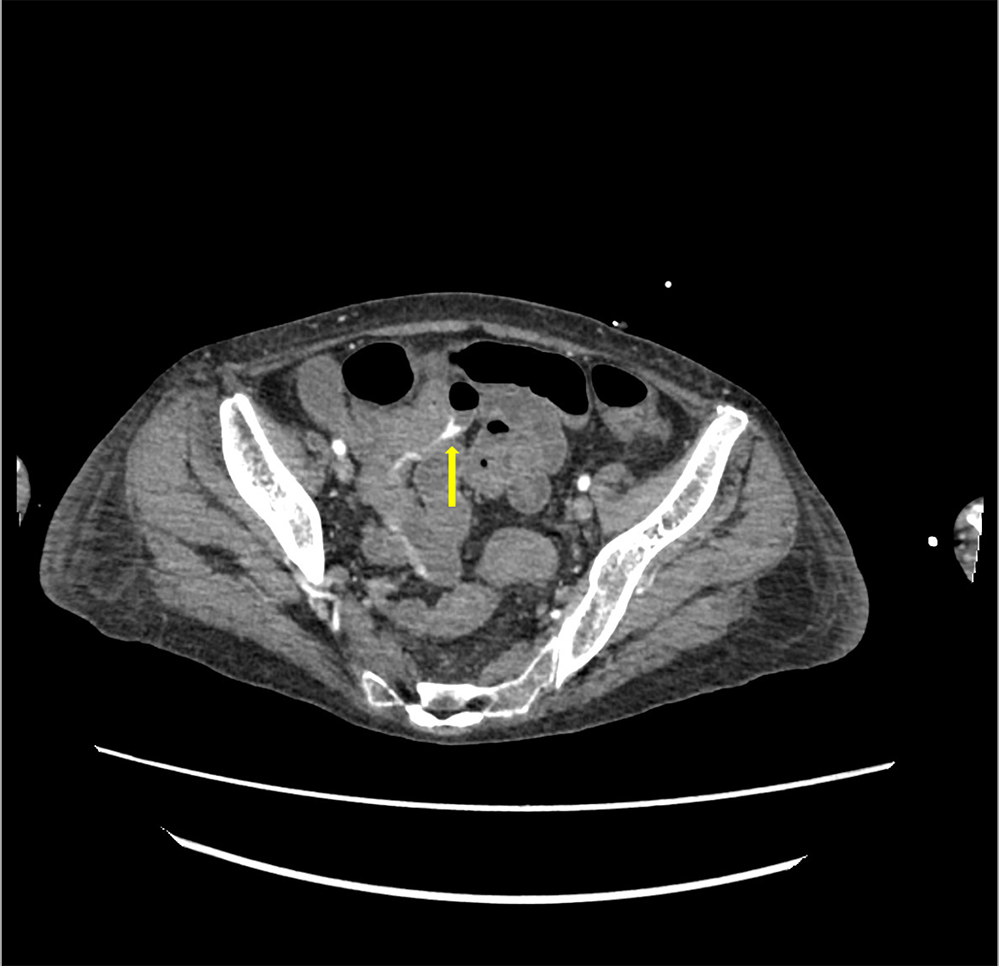

サイトメガロウイルス感染症を背景に下血がみられ消化管出血が疑われた。出血源の精査目的に造影CTが施行された。造影CTにて回腸で造影剤の血管外漏出像がみられ、出血源と考えられた。

消化管出血において、新鮮なものであれば単純CTで消化管内の血球成分が高吸収を示し、出血の有無については判別できることもあるが、出血源の同定はしばしば困難となりうる。この場合造影ダイナミックCTによる精査が必要となる。造影CTを撮像することで、出血源の同定や出血の程度を評価することができ、経カテーテル的血管塞栓術が検討される場合に責任血管までのアクセスルートも確認することが可能である。

撮影時の注意点として、造影CTのみを撮像してしまうと消化管内に高吸収を示す残渣や憩室内の糞石などがみられた場合に造影剤の血管外漏出像との判別が困難となることがあるため、同時に単純CTもあわせて撮像することで判別の補助となりうる。また下部消化管出血はしばしば間欠的に出血するため、造影CT撮像のタイミングで出血が止まっていれば出血源の同定が困難となることがあり、注意が必要である。